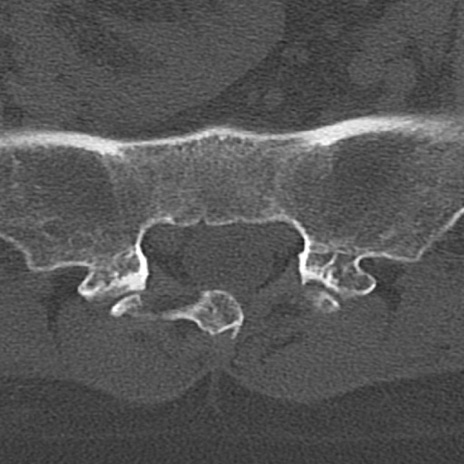

【整形】TIPS症例4 腰椎CT(横断像)

腰椎CT

冠状断像